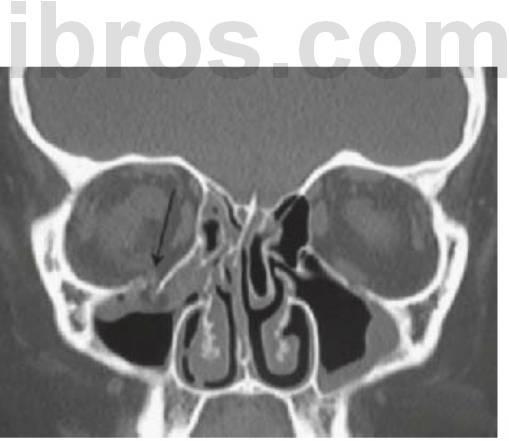

Puede que las fracturas del cóndilo mandibular se infradiagnostiquen en niños, pero suponen hasta dos tercios del total de las lesiones mandibulares y por lo general, suelen producirse por un traumatismo en el borde inferior del mentón. Si se produce una fractura subcondílea, la cabeza del cóndilo se desplaza de forma anteromedial por acción del músculo pterigoideo lateral. Dependiendo del desplazamiento de los fragmentos y de la postura compensatoria de la mandíbula, podría producirse una desviación del mentón hacia el lado afectado, no producirse desarmonías oclusales y quizá un sangrado desde el meato externo, debido a la perforación con la cabeza del cóndilo de la pared anterior del conducto auditivo (v. fig. 7.7C, D). Un otorrinolaringólogo deberá estudiar el sangrado o la secreción desde el oído, pero está contraindicada la succión del meato externo debido a la potencial alteración de la cadena osicular, que podría ocasionar la perforación de la membrana timpánica. Se ha citado algún caso de desplazamiento de la cabeza del cóndilo hacia la fosa craneal media pero es infrecuente.

Debido a que el cuello del cóndilo es relativamente más ancho en los niños y tiene un volumen mayor de hueso esponjoso, las fracturas de la superficie articular son más habituales que en los adultos. En los casos de fractura intracapsular (figs. 7.5, 7.9), el seguimiento durante años permite detectar cualquier alteración de su crecimiento, y en los casos en que aparezca una limitación de la apertura o una anquilosis franca, se recomienda una intervención temprana con un injerto costocondral.